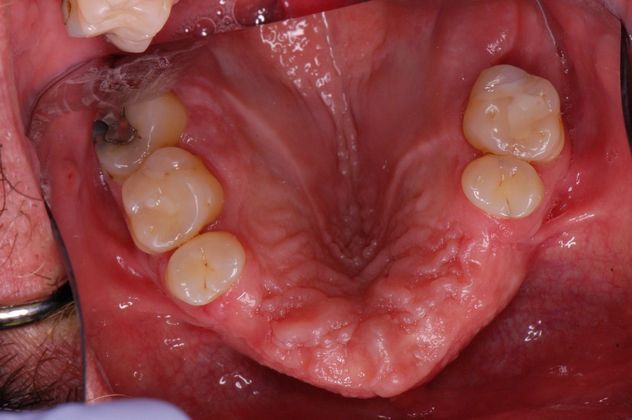

Dental Implants: Case 5 - Before

Before

Patient had front teeth missing since very young. 4 implants were placed and a fixed bridge was fabricated with a terrific outcome!